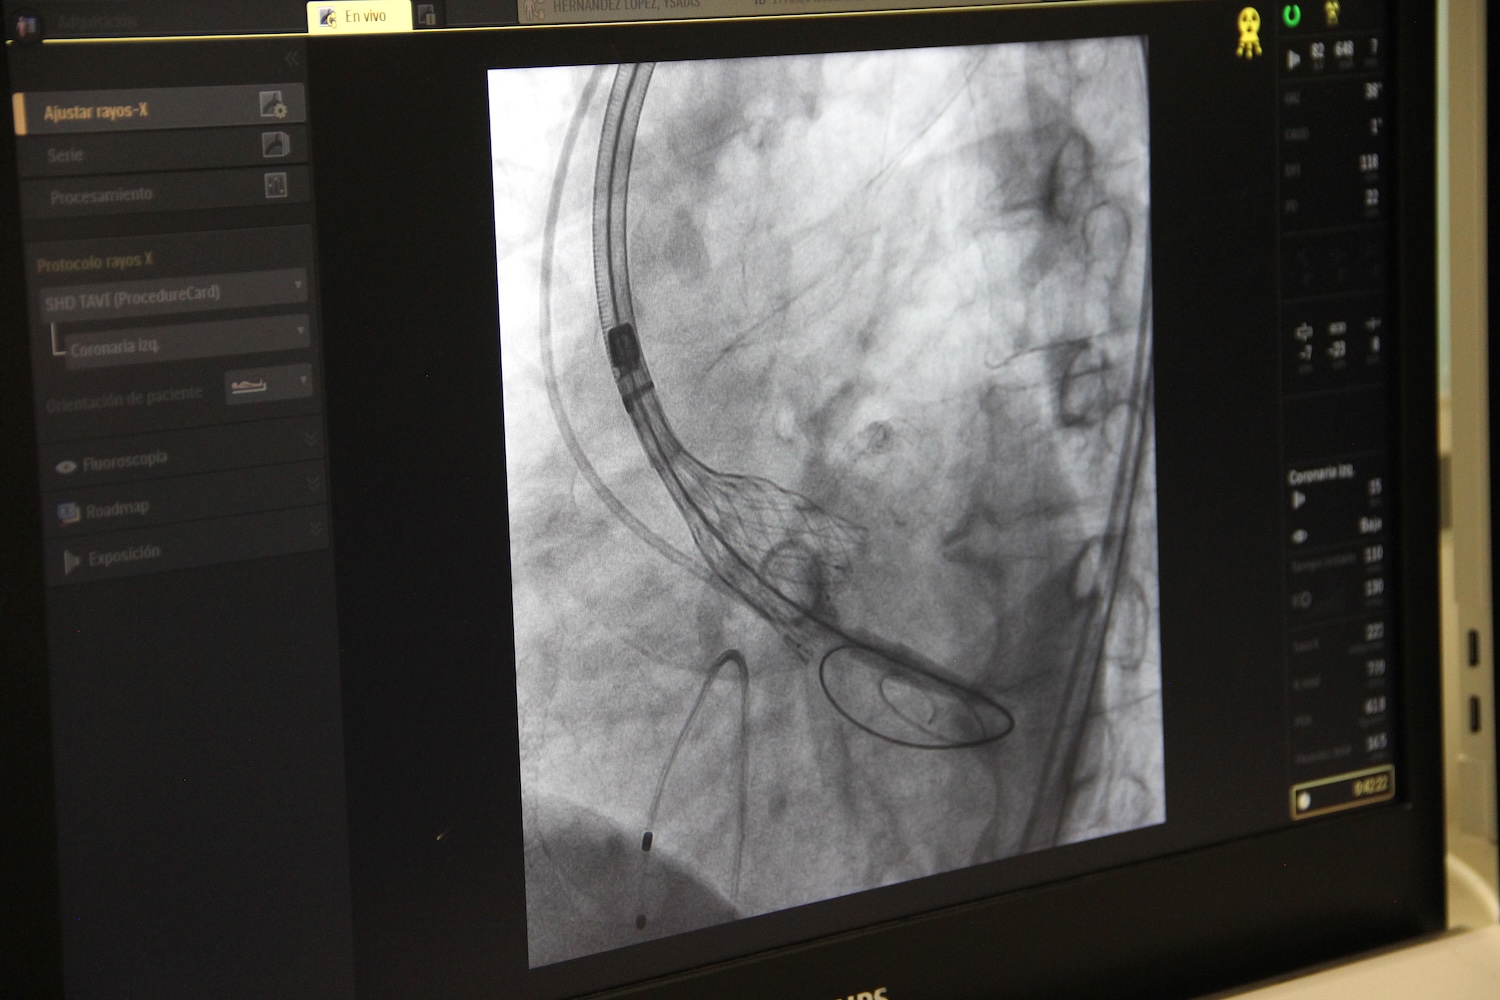

El Hospital General Regional (HGR) número 2 “El Marqués” del Instituto Mexicano del Seguro Social (IMSS) en Querétaro realizó su primer procedimiento de reemplazo valvular aórtico transcatéter, en un paciente masculino de 72 años, quien padece una estenosis valvular aórtica severa, gracias al trabajo conjunto con especialistas del servicio de Hemodinamia del Centro Médico Nacional (CMN) Siglo XXI.

Bryant Andrés Álvarez Salazar, cardiólogo intervencionista de la Sala de Hemodinamia del HGR número 2, señaló que este procedimiento consiste en “aprovechar los accesos vasculares, las arterias femorales para avanzar dispositivos de alto calibre, a través de la válvula aórtica y posicionar una nueva válvula para reemplazar la previa”.

“A este paciente lo conocimos en diciembre, a quien le realizaron una angioplastia de tres arterias (coronaria), que se hizo como paso previo a lo que se estaba esperando, que era colocar una válvula percutánea”, indicó Estrada Gallegos.